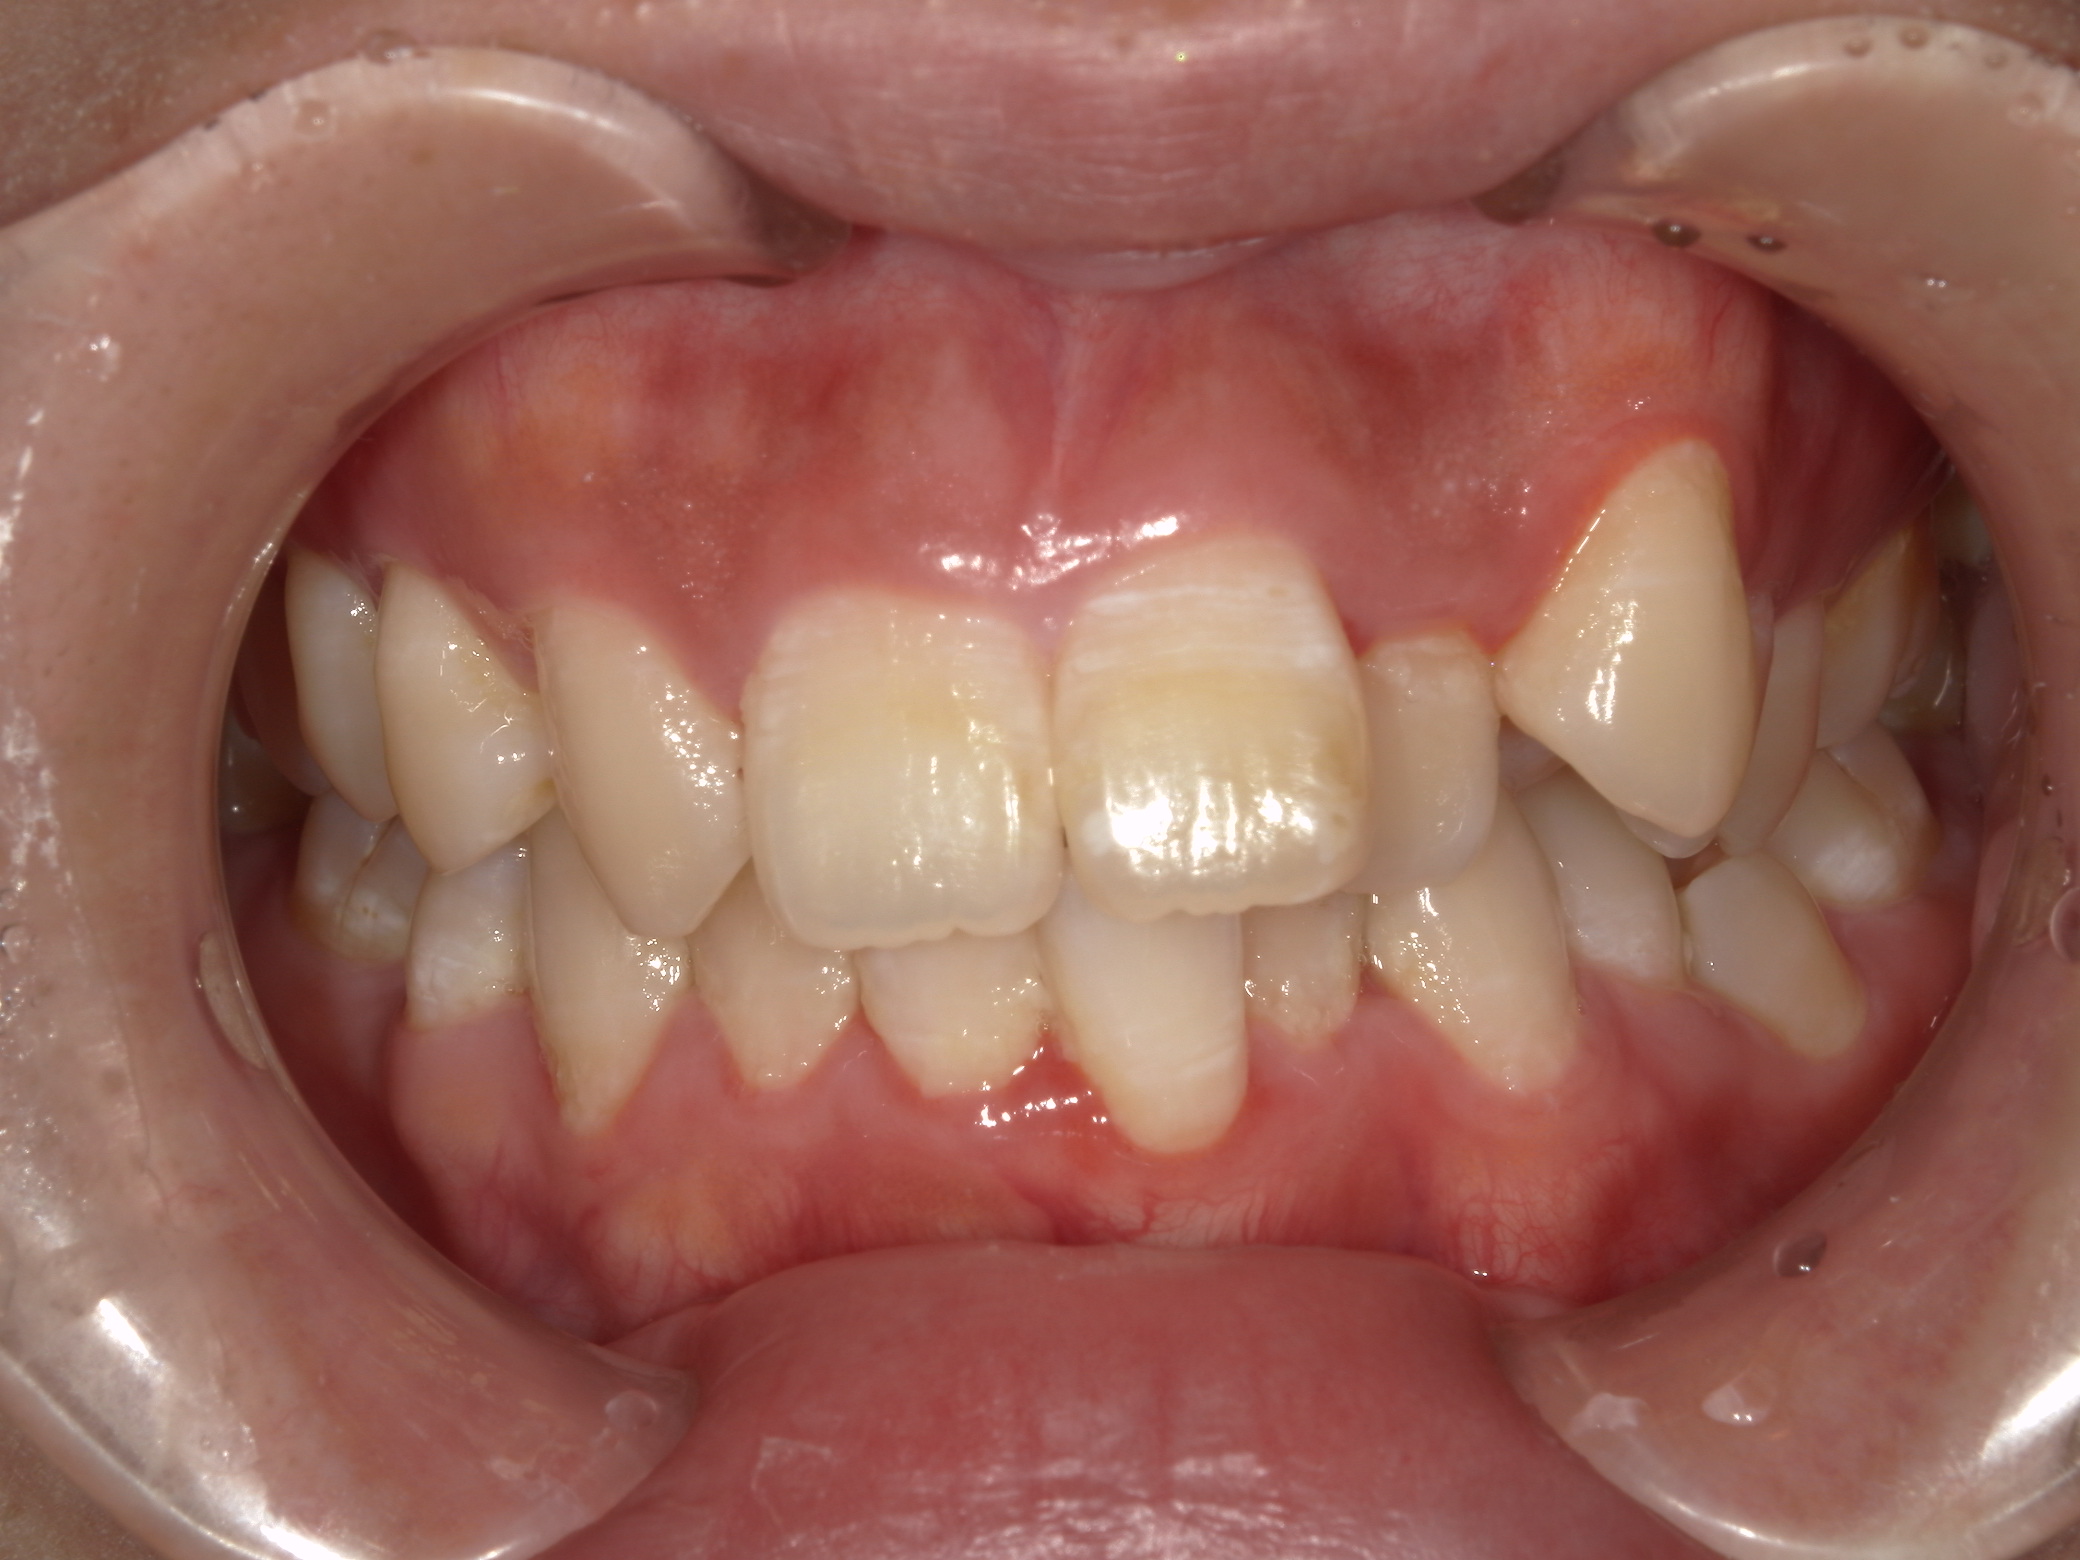

前歯の歯並びの乱れ(叢生)が気になる

| 年齢・性別 | 25歳女性 |

|---|---|

| 主訴 | 前歯の歯並びの乱れ(叢生)を気にされて来院された。咬み合わせや審美的な改善を希望されていました。 |

| 治療期間・回数 | 4年5ヶ月・30回 |

| 費用 | 1100,000円(税別) |